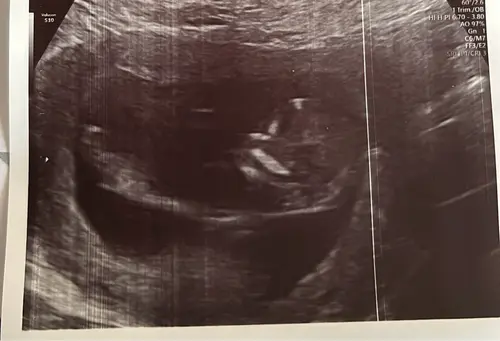

12 weken 🩵🩷 Op het bovenste beeld zie je een handje 😍